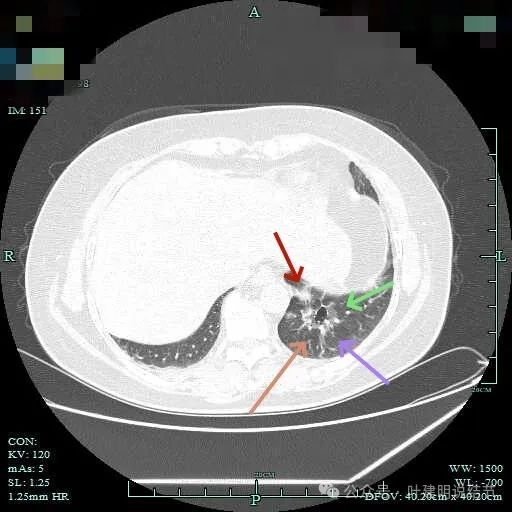

实性成分占比较高,边上有明显磨玻璃成分,说明含贴亚型。

灶内有小空泡征,磨玻璃部分轮廓与边界清,实性部分虽明显但毛刺征或收缩力等均不明显。

磨玻璃成分以及灶内空泡征。

灶内细支气管扩张明显,实性成分缺乏收缩力,考虑腺泡亚型。